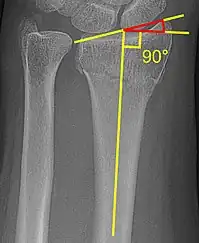

Radial inclination

The radial inclination of a distal radius fracture is shown in red in image at right. The angle is measured between:[4][5]

- A line drawn between the distal ends of the articular surface of the radius on an AP view of the wrist.

- A line that is perpendicular to the diaphysis of the radius.

Radial inclination is normally 21-25°.[6]